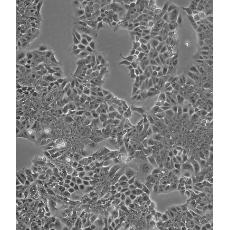

HCT-15 [HCT15]

產品名稱 HCT-15 [HCT15]

中文名稱 人結直腸腺癌細胞

組織來源 結腸腺癌;男性

細胞種屬 Homo sapiens, human

生長特性 adherent

培養基 RPMI-1640+10% FBS+1% P/S

形態特征 epithelial

細胞描述 HCT-15 cells are CSAp negative(CSAp-).The cells are positive for keratin by immunoperoxidase staining.